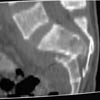

MR2

A 28 year old male jumped from the 4th floor on 11-25-2000 sustaining an L1 burst fracture that has been fixed anteriorly by the neurosurgeon with a strut between T12 and L2. A Kaneda device was placed anteriorly as well. My concern is the pelvic ring injury. There are bilateral sacral fractures through the foramen and a transverse element through the sacrum between S2 and S3. the lower part of the sacrum is displaced forward. Anteriorly there are right superior and inferior pubic rami fractures.

He also has bowel and bladder sxs. The neurologic injury could be from the L1 burst or from the sacrum or both.